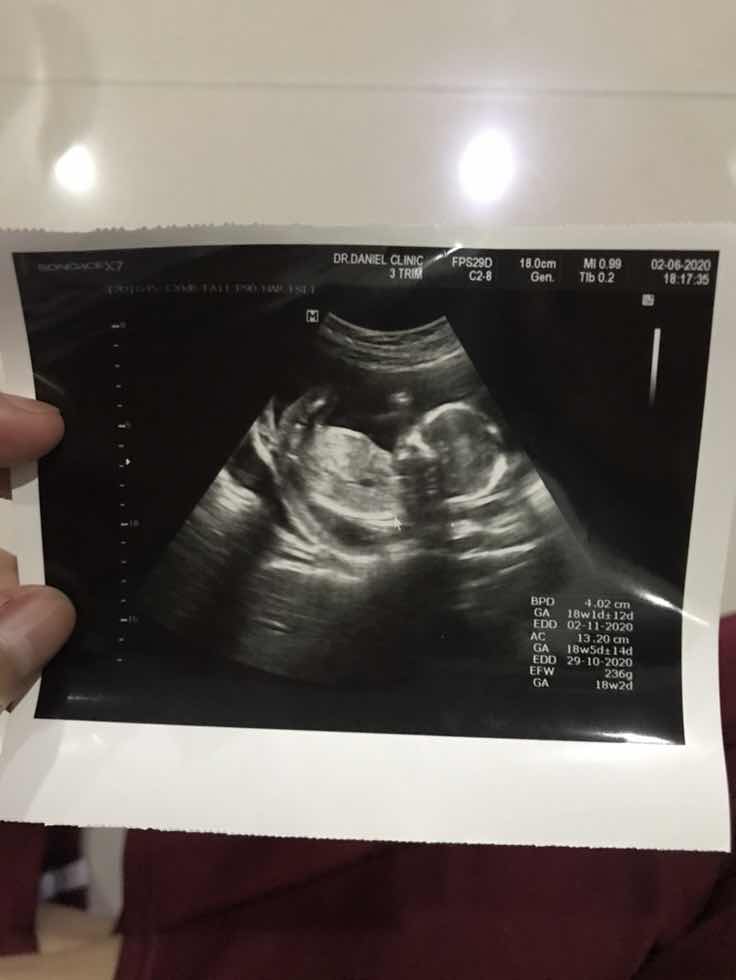

16 พ. ย 63 ค่ะ